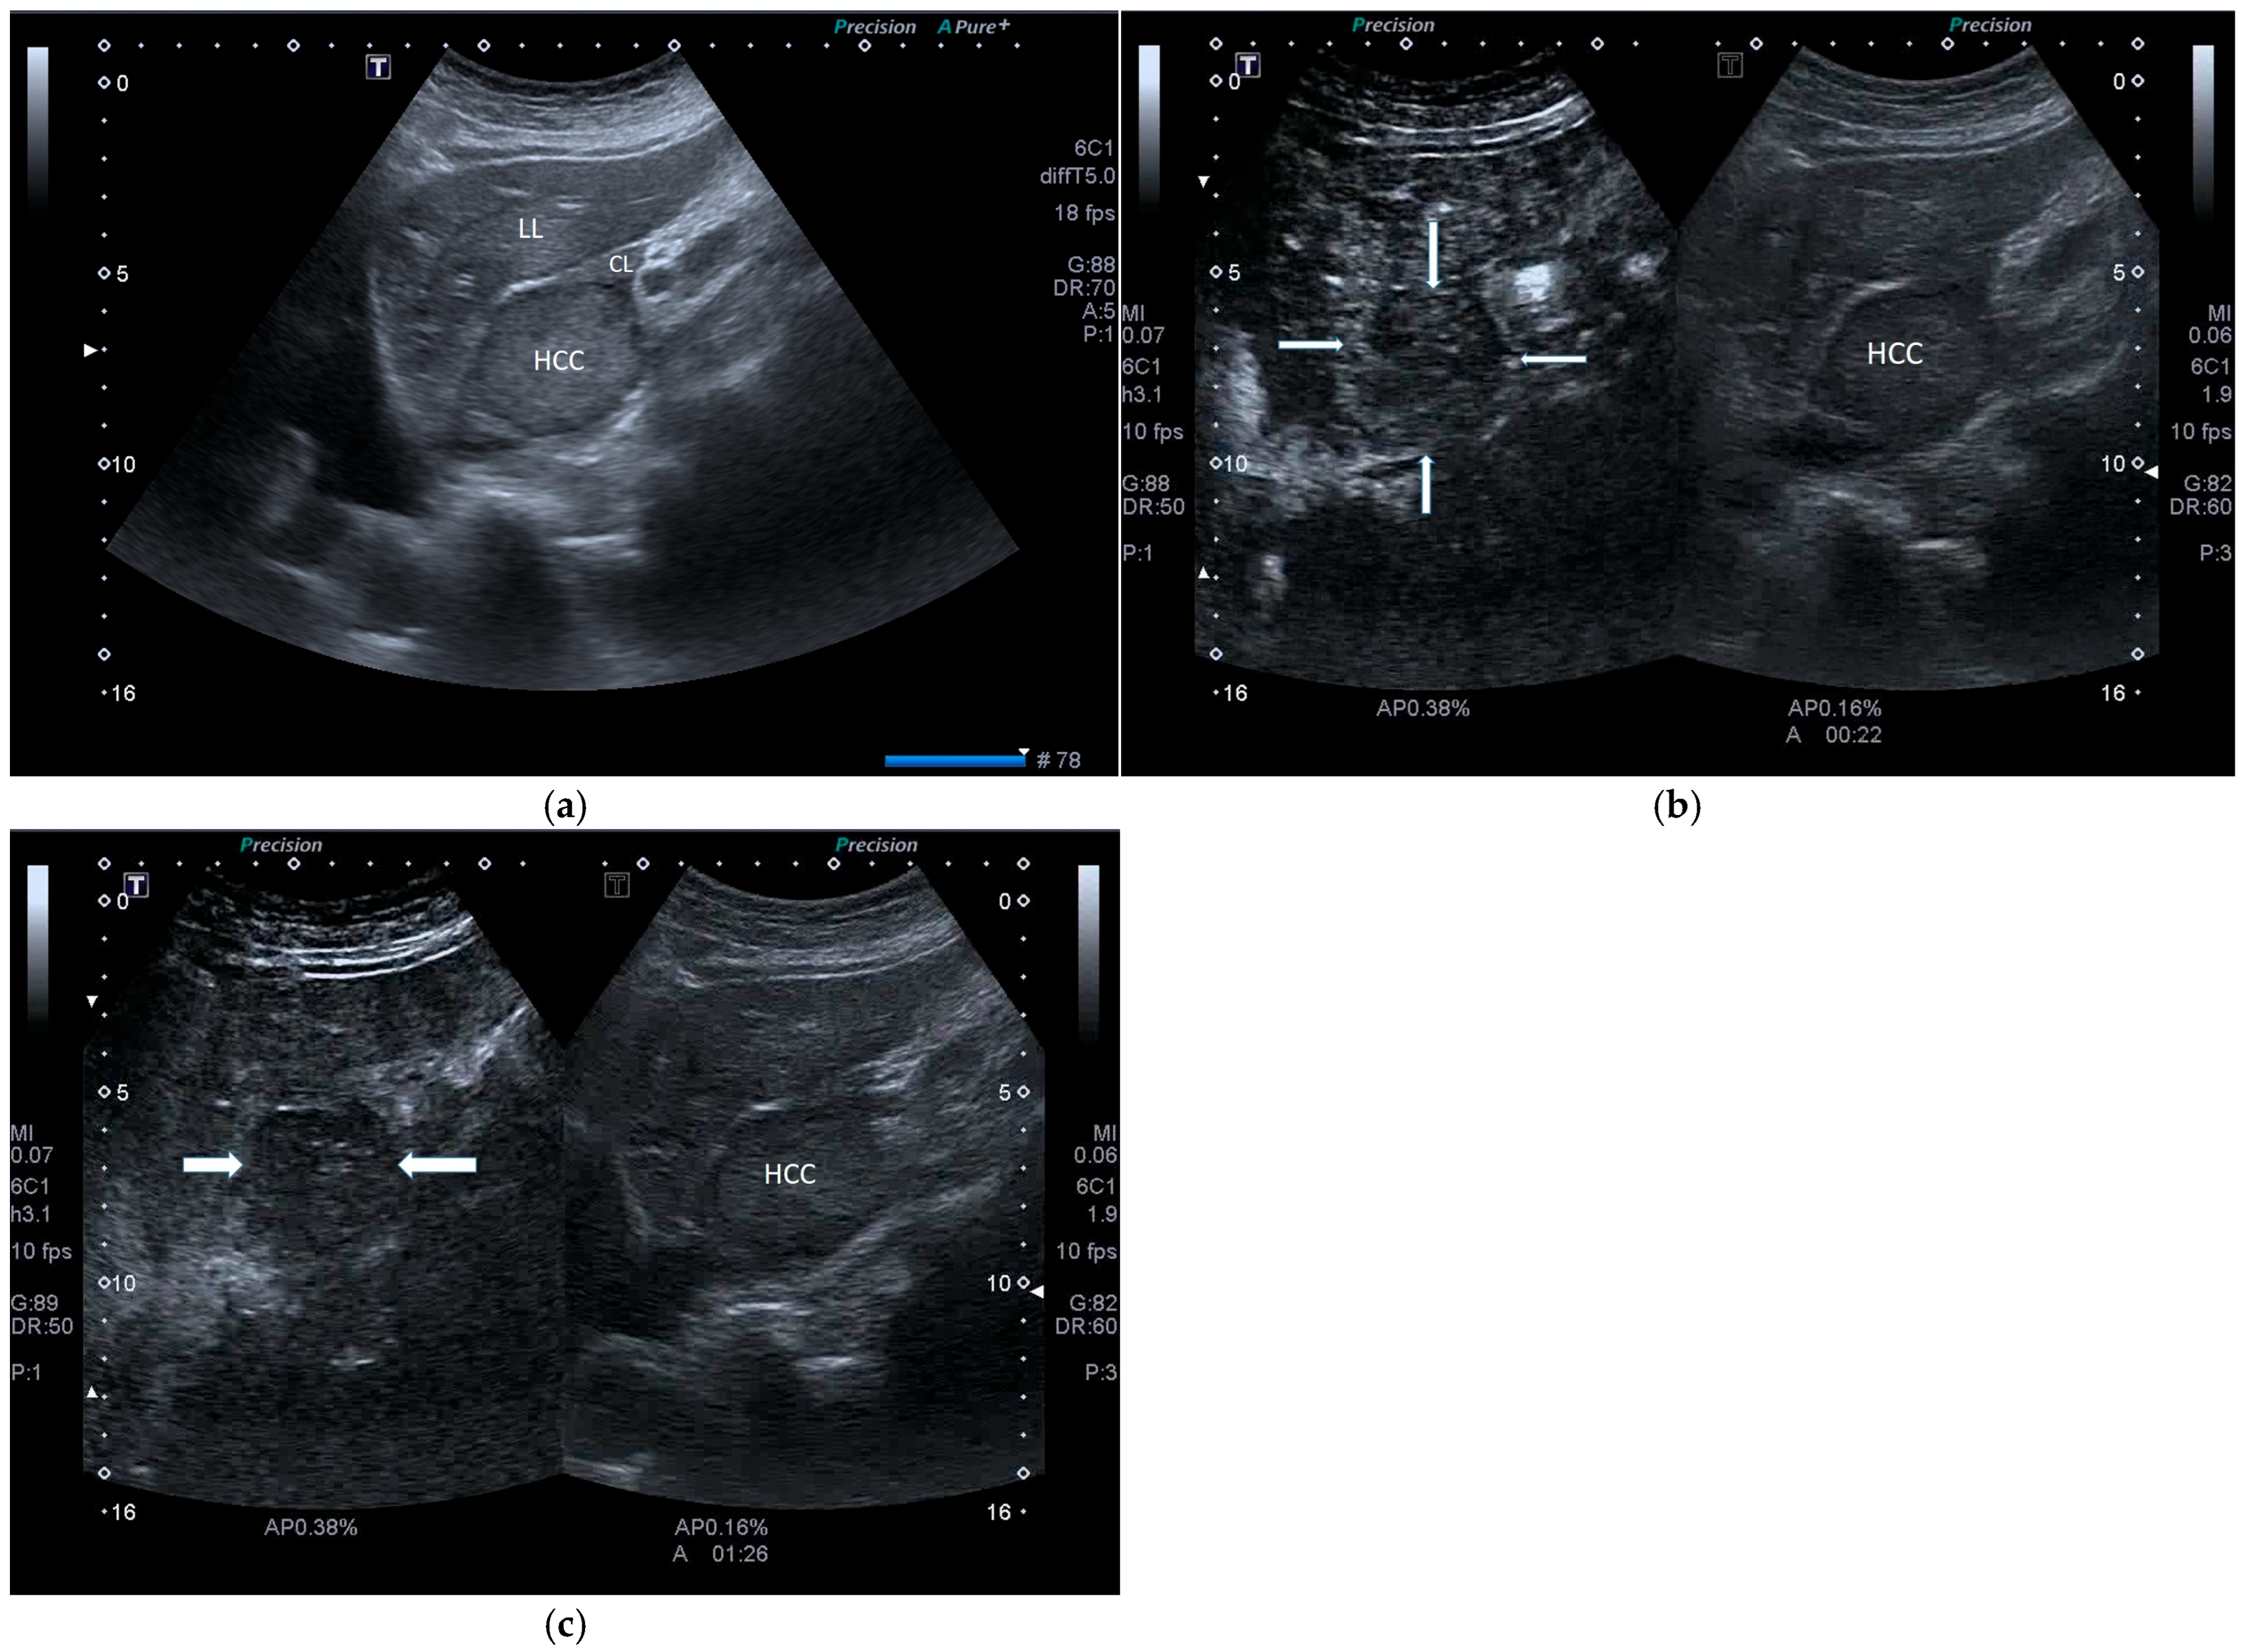

| POST-VIRAL HCC | MASLD HCC |

|---|---|

|

| |

| These characteristics would be focused more on the lack of malignancy rather than HCC. | |

| Need for liver biopsy to make the diagnosis. |